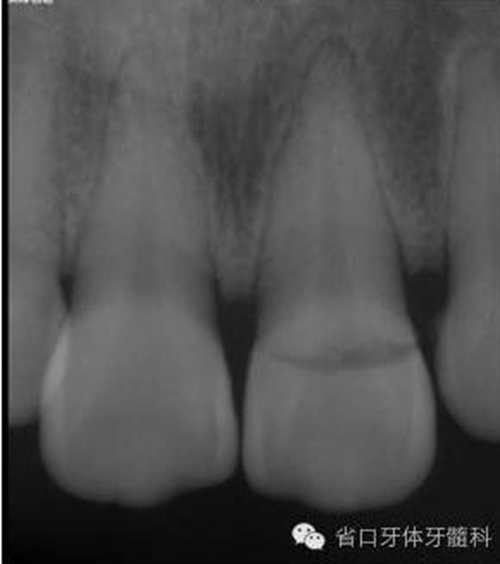

圖1. 術(shù)前口外照片

圖3. 術(shù)前X線片